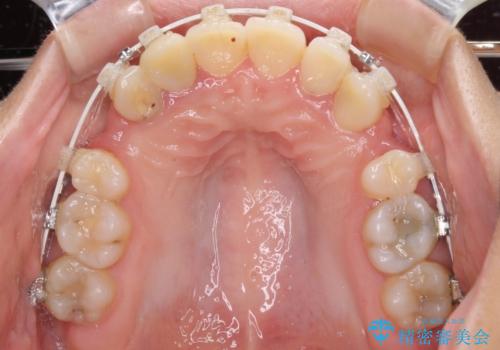

開咬と前突を改善 ワイヤー装置での抜歯矯正

- 矯正装置

- 審美装置

口元の突出感を改善するため、第一小臼歯を抜歯して口元を引っ込めることとしました。

一般的には上下左右の第一小臼歯4本を抜歯しますが、下顎に対して上顎が前方に位置しているため、まずは上顎小臼歯2本を抜歯し、治療経過を見て下顎小臼歯を抜歯するかどうかを決めていくこととしました。

元々むし歯の処置歯が多く、神経を取り除いている歯が多くありましたが、どうやら右上の前歯と小臼歯は外傷により神経を失った可能性があり、抜歯したスペース前後の歯が全く動かない状態でした。

結果として下顎の小臼歯は抜歯せず、右上の抜歯スペースはむし歯処置を兼ねてオールセラミックブリッジにて補綴治療を行うこととしました。

動かない歯での停滞や、出産と子育てなどにより治療期間は長期化しましたが、整った歯列にて仕上げることができました。